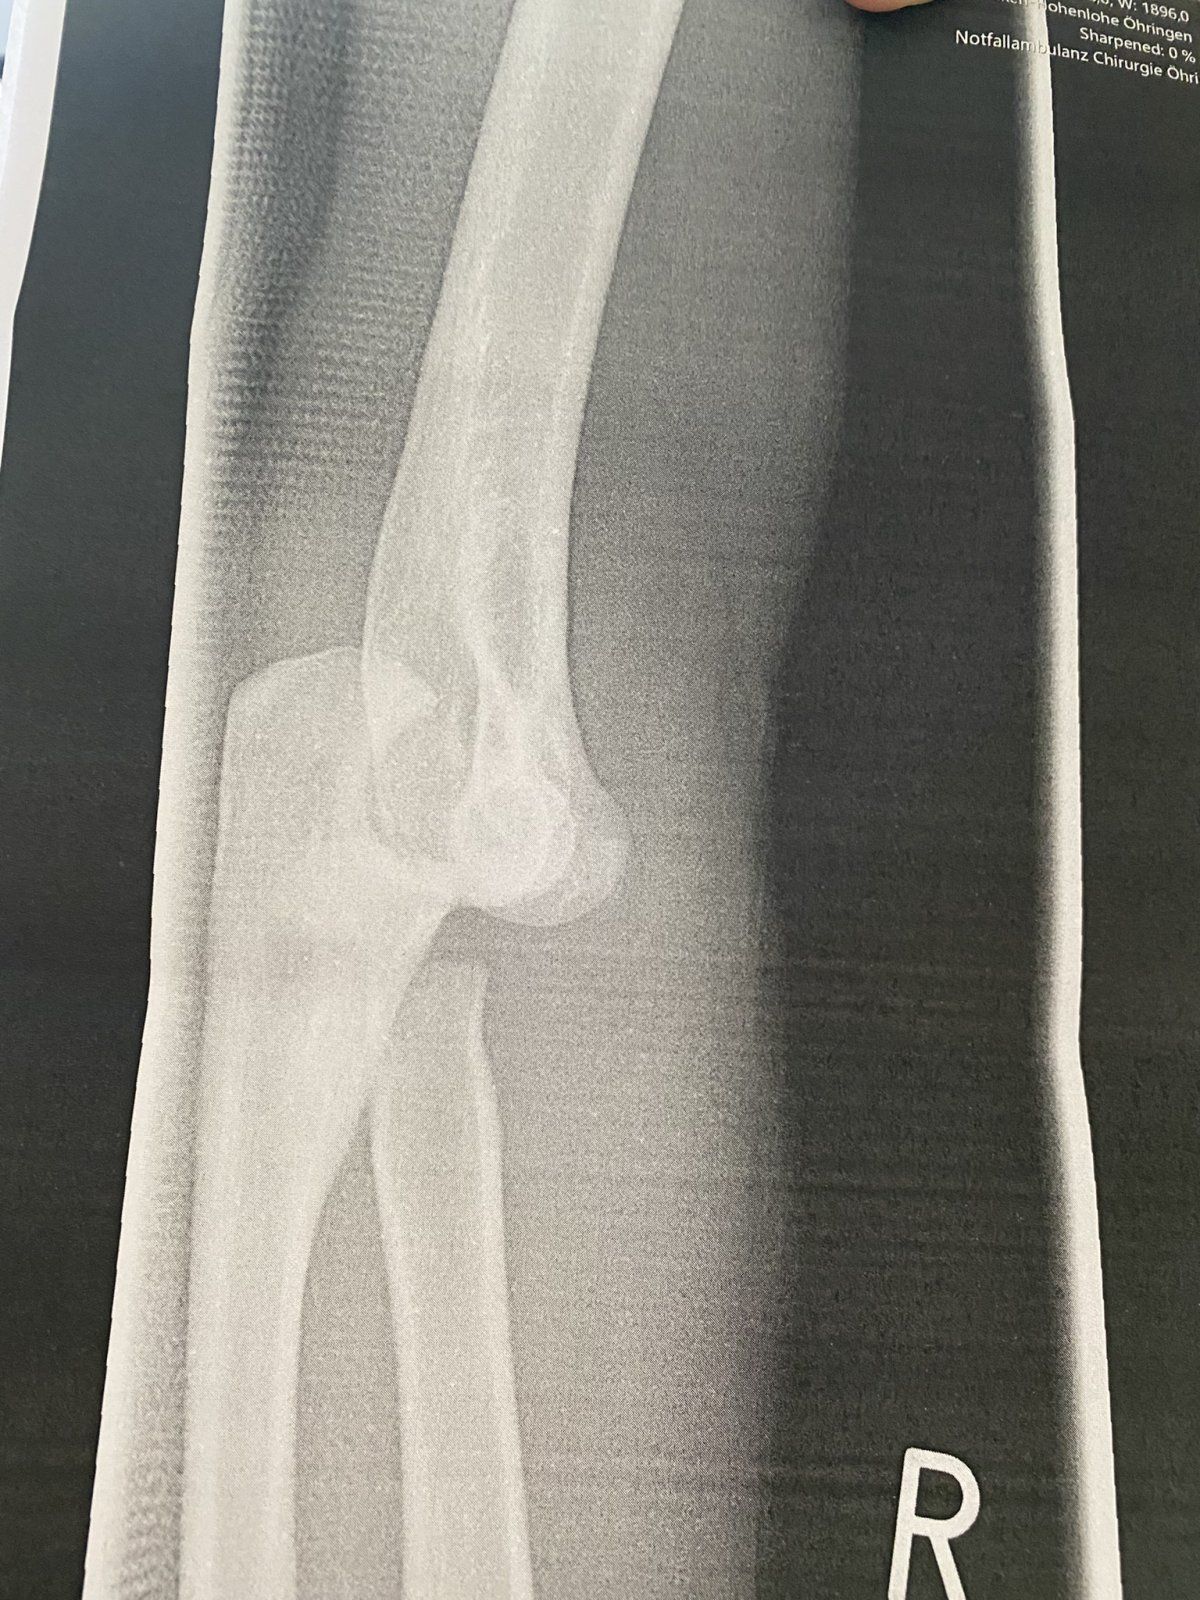

Hallo zusammen, hier scheine ich ja im richtigen Thread zu sein. Vielleicht gibt es Erfahrungswerte zu folgendem Fall. Habe mir das innere Seitenband im Ellenbogen gerissen und einen Muskelfaserriss zugezogen. Am Knochen wurde eine Fisur fest gestellt. Das Ganze ist jetzt 8 Wochen her. Nach einer etwas seltsamen Reise von Arzt zu Arzt hiess es letzendlich es wird nicht operiert. Ich mach 3x die Woche Physio und mach die Übungen fleißig. Allerdings dauert es gefühlt eeewig den Arm wieder in die Streckung und Beugung zu bekommen. Es fehlen in der Streckung noch 25° und schmerzt dann im Gelenk. Und generell wird es nur langsam besser mit der Bewegung. Die Kraft im Arm ist nicht wirklich vorhanden. Nun meine Frage... ist so etwas bei Euch vollständig geheilt. Es kann bei einer konservativen Behandlung zu Instabilität kommen - gibt es da Erfahrungswerte? Gerade im Zusammenhang mit dem Biken und der Haltung auf dem Rad?